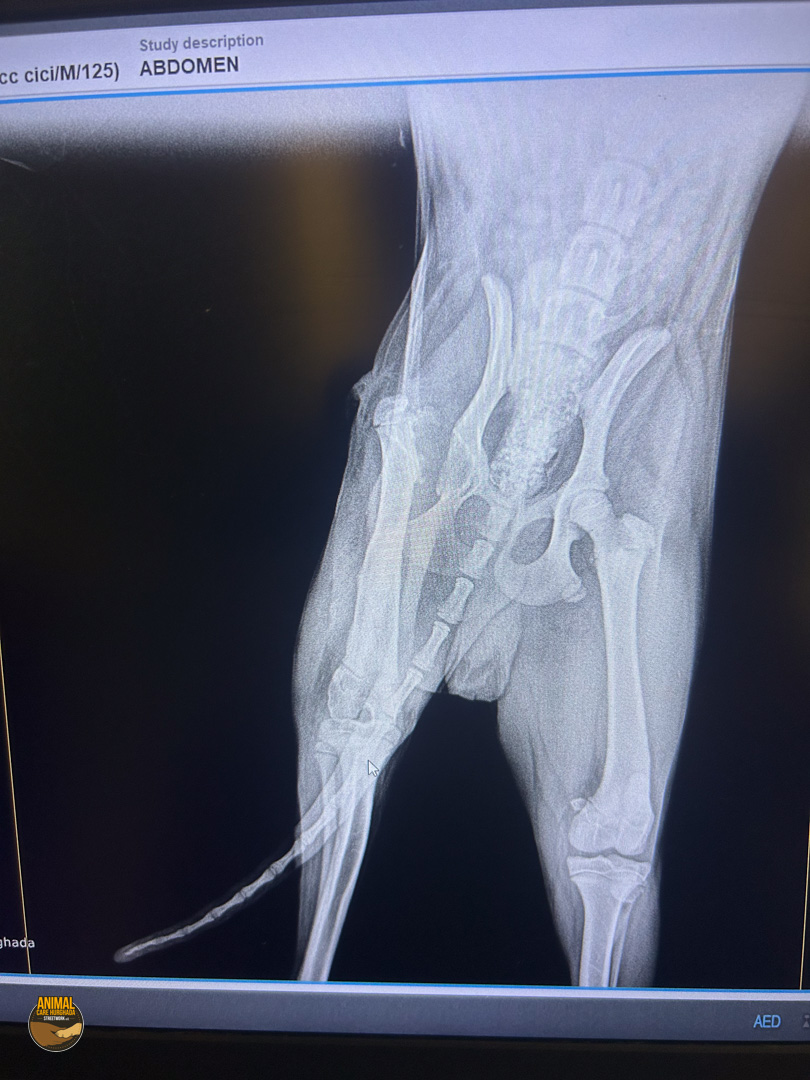

Pepe hat bereits einiges hinter sich – doch heute blickt er voller Zuversicht nach vorn. Eine aufmerksame Frau fand ihn verletzt auf der Straße, sammelte ihn liebevoll ein und brachte ihn in eine „Tierklinik“. Dort wurde Pepe operiert – leider jedoch nicht fachgerecht. Als er zu uns kam, wussten wir nicht genau, was bei ihm gemacht worden war. Also fuhren wir wenige Tage später mit ihm in die „Top Vet’s Clinic“ zur weiteren Untersuchung. Die Röntgenbilder brachten traurige Gewissheit: Pepe hatte sowohl eine gebrochene Hüfte als auch einen Bruch des Oberschenkelknochens – beides wurde in der ersten Klinik zwar operiert, allerdings leider sehr schlecht. Das Bein war steif, schmerzhaft und bereitete ihm große Probleme im Alltag. Schweren Herzens, aber in seinem besten Interesse, entschieden wir uns dazu, das Bein zu amputieren. Und siehe da – seitdem geht es Pepe endlich wieder gut!